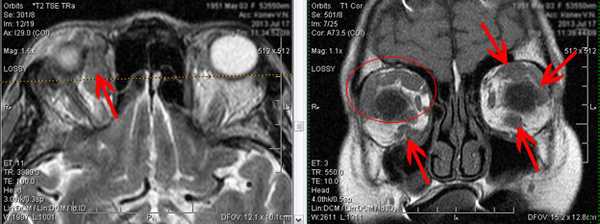

5. Объемные образования орбит.

В орбитах с обеих сторон, более выражено справа, определяются множественные дополнительные образования. Образования интимно прилежат к стенкам глазниц, мышцам глаза. Часть из них - расположены изолированно в орбитальной клетчатке без достоверных признаков прилежания к структурам глазниц.